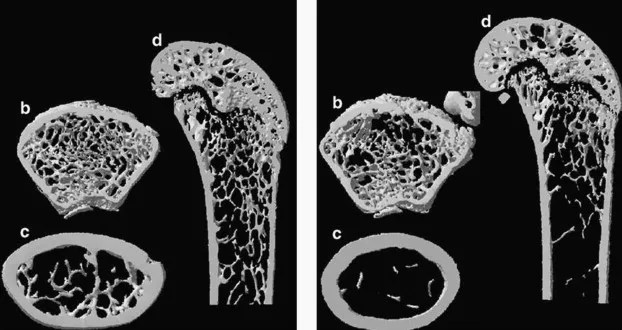

- Type 1 (Postmenopausal): Estrogen ↓. Affects mainly trabecular bone.

- Type 2 (Senile): Age-related (typically > 70 years). Affects trabecular & cortical bone.